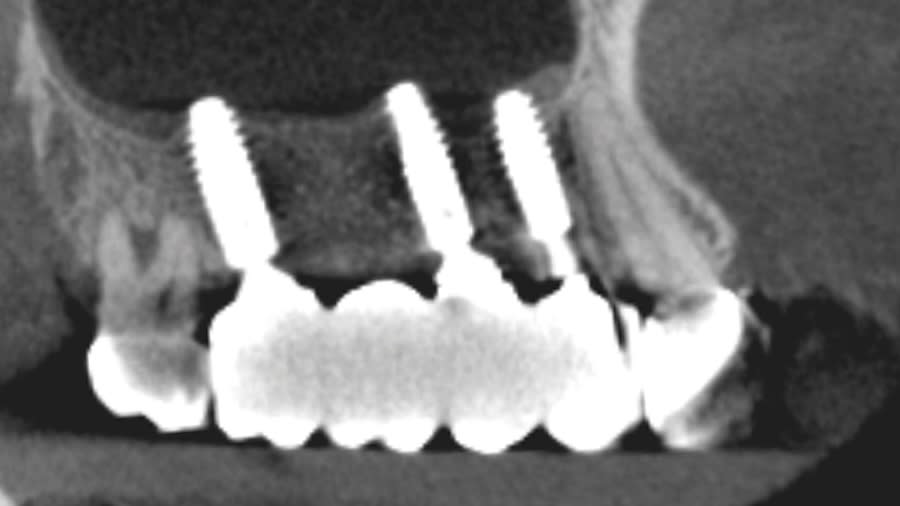

Case 1 (Figure 3 through Figure 24) depicts a 3-year follow-up of combined osseodensification sinus protocol IV in a severely resorbed maxillary ridge with ≤0.5 mm bone height in molar sites and horizontal deficiency at the first premolar site, using a two-stage approach for implant placement.

Case 2 (Figure 25 through Figure 36) illustrates a 3-year follow-up of the osseodensification sinus protocol IV in a severely resorbed right maxillary ridge with <0.5 mm bone height in molar sites, using a two-stage approach for implant placement.

Case 3 (Figure 37 through 44) shows a case of significant trauma history with a 3-year follow-up of the osseodensification sinus protocol IV in a severely resorbed right maxillary ridge with ≤0.5 mm bone height in molar sites, using a two-stage approach for implant placement.

The presented protocol describes a crestal sinus elevation procedure using osseodensification burswith vertical stops (Versah) in severe cases with <2 mm of residual bone as a predictable technique, with successful bone regeneration for second-stage implant placement with subsequent stable peri-implant bone level at 3-year follow-up. This technique, thus, offers a simplified, minimally invasive, and less traumatic method for sinus floor elevation in cases with severe residual bone height loss.